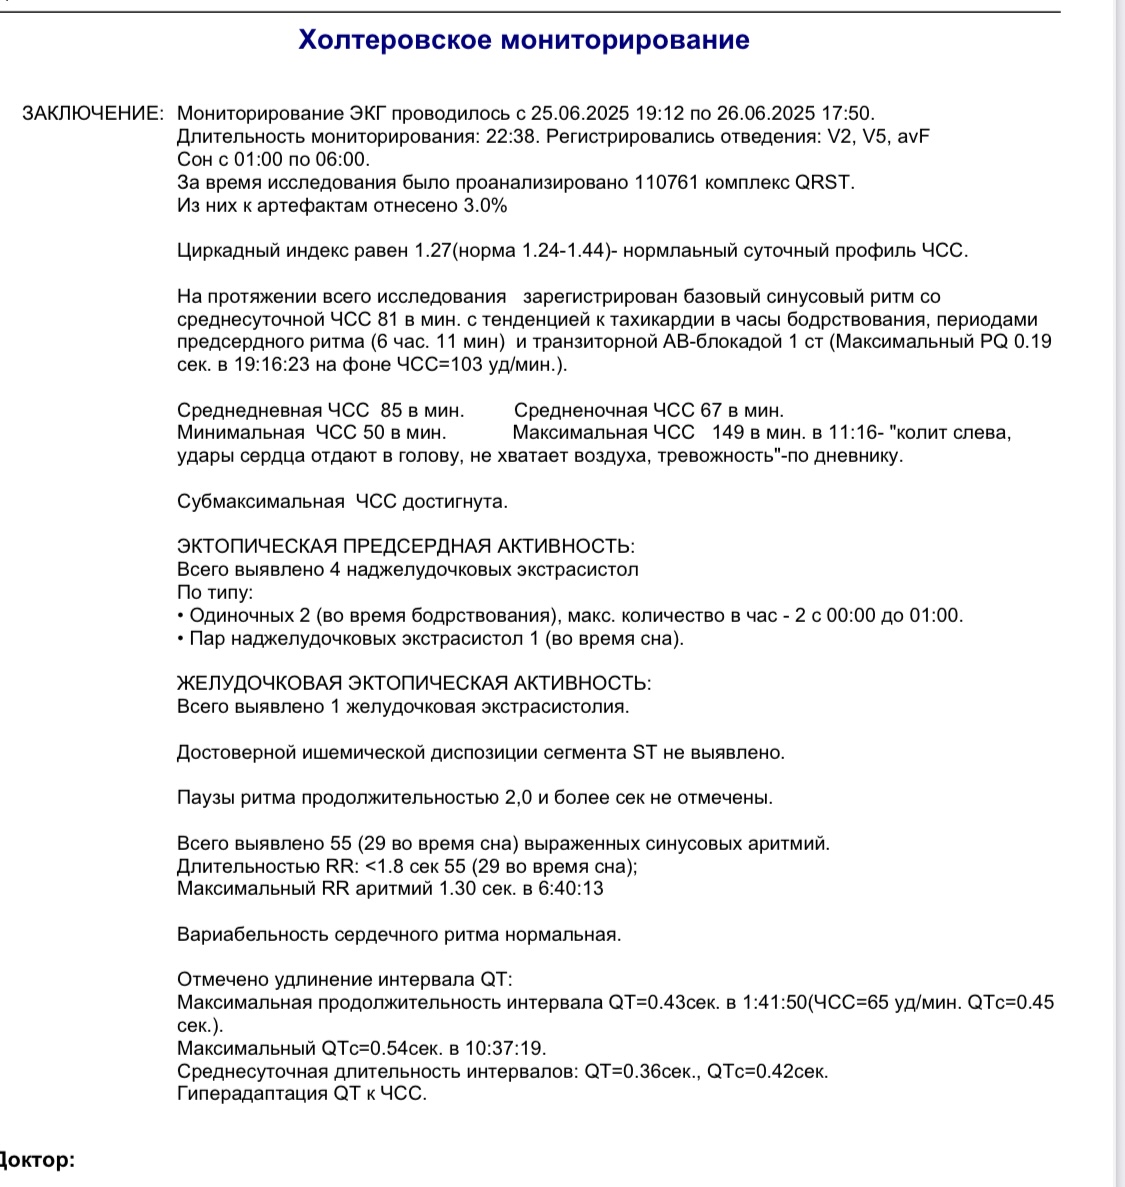

Расшифровка холтера

|

|

👍 0 👎 |

Расшифровка результатов холтера

|

|

👍 0 👎 |

Есть ли изменения по холтеру и вэг?

|